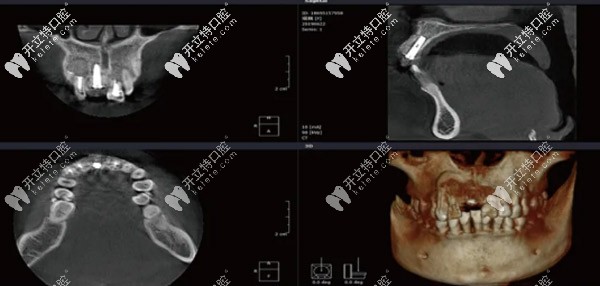

CBCT顯示11骨量高度18mm,近遠(yuǎn)中骨間隙10mm,唇舌側(cè)間隙6.3mm

在植體頂部和唇側(cè)植入Bio-Oss骨粉,壁鈦網(wǎng)加固13.12.21空腔內(nèi)植入Bio-Oss骨粉,覆蓋骨膜,嚴(yán)密縫合創(chuàng)口,手術(shù)當(dāng)日CBCT顯示種植體位置方向不錯(cuò),骨粉填充效果好,且13.12.21無松動(dòng)。

CBCT顯示種植位置方向良好,植骨區(qū)域成骨效果顯著。局部麻醉后,11牙槽頂和鄰牙齦緣切開后翻瓣,取出鈦網(wǎng),放入愈合基臺(tái),縫合。